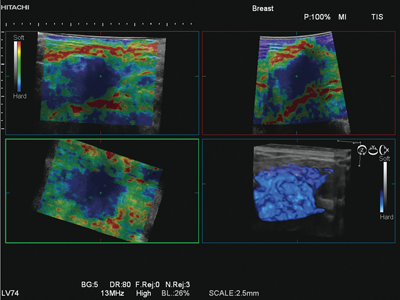

■4D Elasto

日立では,世界に先駆けて,リアルタイムにElastographyを3D表示する機能“4D Elasto”を超音波診断装置に搭載した(図5)。これは,より進化した“Ultra BEU(Ultrasound Broadband Engine 2nd Generation)”の高い演算能力により実現した。

プローブを機械的に揺動させることで,歪みのボリュームデータをリアルタイムに取得し,組織の硬さ情報を画像化する。ボリュームデータから,硬い領域と,軟らかい領域を個別にレンダリング処理することで,立体感を創出している。

図5 4D Elasto